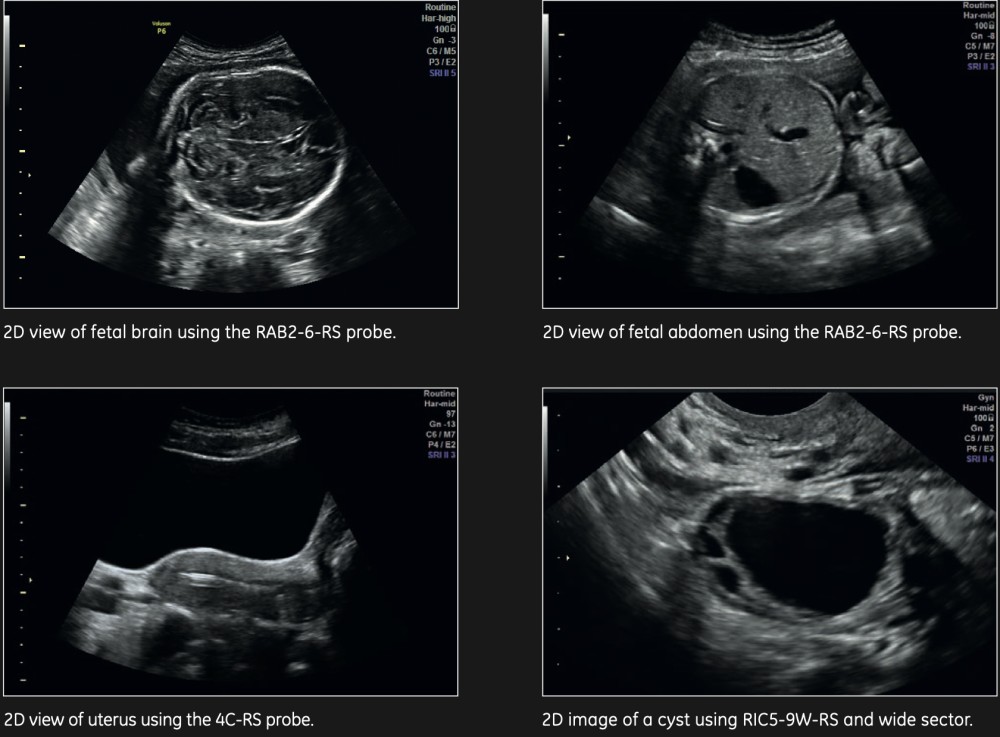

Real vaxtda 3D və 4D görüntüləmə

Proqram Seçimləri: SonoNT™, SonoAVC™, SonoVCAD, STIC, Uterus VCI, IOTA, Omniview

Həcmi Görüntüləmə: Seksional müstəvilərdə volumetrik vizualizasiya, rendering texnikaları (şəffaflıq, səth, skelet)

Voluson P6 kompakt və yüksək performanslı ultrasəs sistemidir, rutin ginekoloji və obstetrik müayinələr üçün idealdır. Yüksək keyfiyyətli 2D görüntüləmə və 3D/4D imkanları təqdim edir, dəqiq nəticələr əldə etməyə imkan verir. 17 düymlük yüksək çözünürlüklü LCD ekran və üç aktiv prob portu ilə məkan məhdudiyyəti olan klinikalar üçün ideal seçimdir. Voluson P6 CrossXBeamSpeckle Reduction Imaging (SRI) kimi texnologiyaları birləşdirərək, aydın və detallı görüntülər təqdim edir.